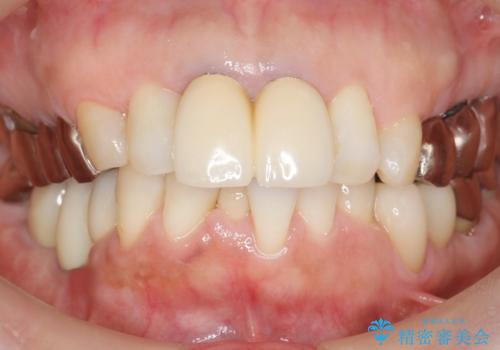

セラミッククラウンの自然な仕上がりと咬み心地に大変ご満足頂けました。

歯がしみる症状もなくなり、外側に出ていた歯が気にならなくなったと喜んで下さいました。

クラウンの種類:オールセラミッククラウン エコノミー